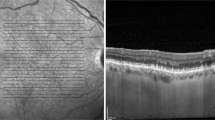

Determination of the Hyperreflective Layer of the Inner Choroid

The hyperreflective layer of the inner choroid was identified when the peak reflectivity of the choroid was located between the choriocapillaris layer and the medium or large choroidal vessels (Figs. 1 and 2). The optical intensity ratio (OIR) of the hyperreflective layer of the inner choroid was defined as the mean OCT reflectivity of the peak reflectivity of the inner choroid, normalized to the mean reflectivity of the vitreous. To obtain the OIR [22] of the hyperreflective layer of the inner choroid, we calculated the peak choroid OIR by dividing the average intensity of the hyperreflective layer of the inner choroid by the mean vitreous intensity. The distance between the RPE-BM complex and the hyperreflective layer was measured. In eyes with extracellular deposits between RPE and BM, the distance between the BM and the hyperreflective layer was measured.

Representative cases of the hyperreflective layer of the inner choroid. In most of the eyes with normal fundus (A) or pachydrusen (B), the peak choroidal reflectance (red arrowheads) was located between the choriocapillaris and a large choroid vessel layer. However, the peak choroidal reflectance was not observed in some eyes with soft drusen (C). The blue and green asterisks indicate the retinal pigment epithelium and choroidal–scleral junction, respectively

Of the 63 subjects with drusen, 35 had soft drusen, and 28 had pachydrusen. The mean age was lower in the eyes with pachydrusen (P < 0.001) (Table 2). The central macular thickness did not differ between the groups (P = 0.958), but the subfoveal choroidal thickness was thicker in the pachydrusen group (P < 0.001). The proportion of eyes with the hyperreflective layer of the inner choroid differed between eyes with soft drusen and pachydrusen (P = 0.001). The hyperreflective layer was observed in all eyes (100%) with pachydrusen but only in 68.6% of eyes (n = 24) with soft drusen (Fig. 3). Drusen were more frequently observed within 500 μm of the foveal center in eyes with drusen than those with pachydrusen (P < 0.001).